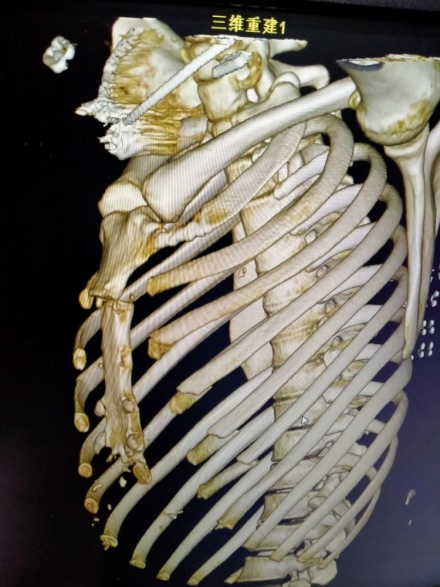

该患者因胸部外伤入住代县医院骨科二病区,术前CT三维重建,诊断:I型胸骨柄体关节脱位。胸骨柄体关节脱位又叫胸骨柄体连接脱位,是一种特殊类型的胸骨损伤,通常是严重创伤的结果,在临床上罕见,常继发心肌损伤。

术前影像